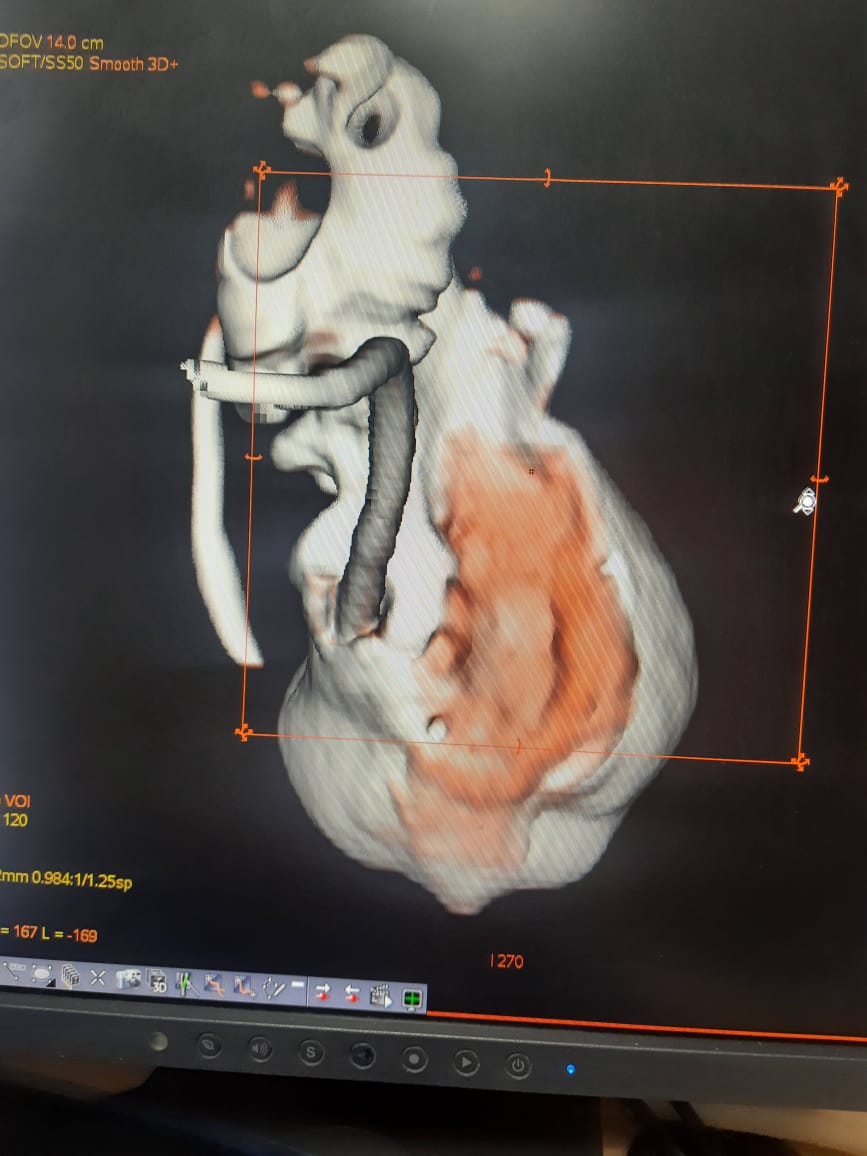

2. Clinical Work at Center